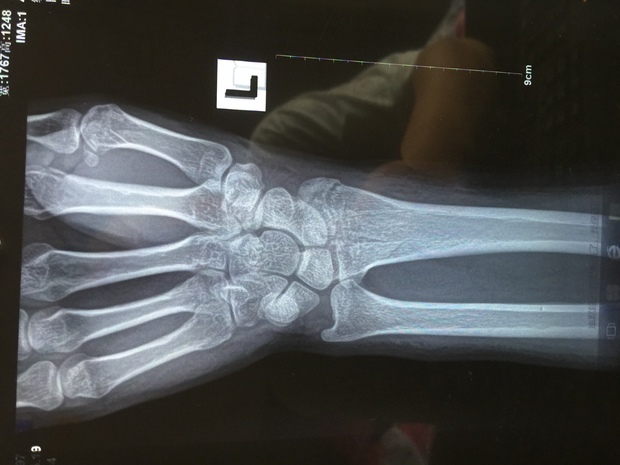

喝断片了,右手腕疼痛肿胀 [病例帖]

入院诊断:左月骨脱位,左舟骨骨折(ct检查发现) 行手法复位,石膏

左腕远端骨折,大神帮帮忙